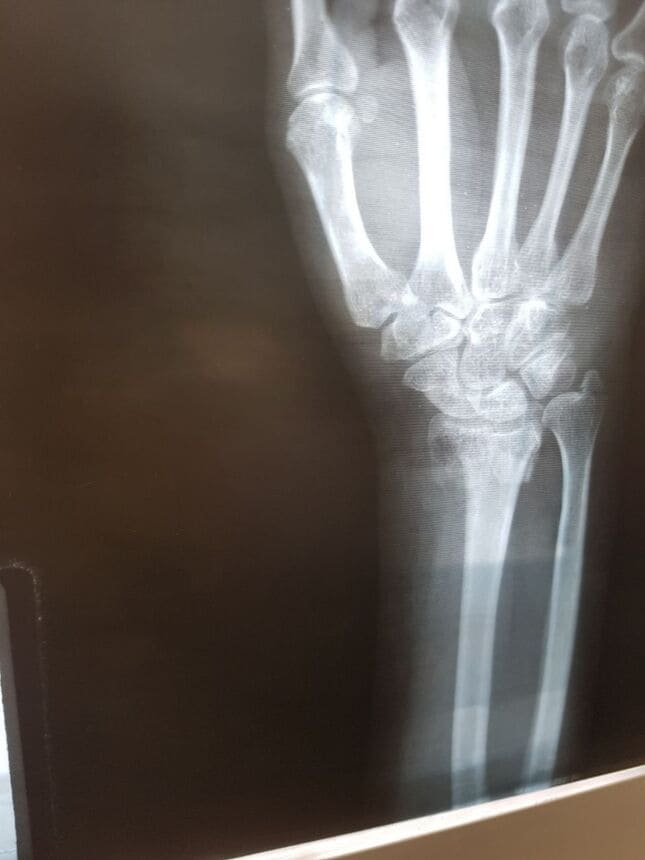

Fractura de radio distal